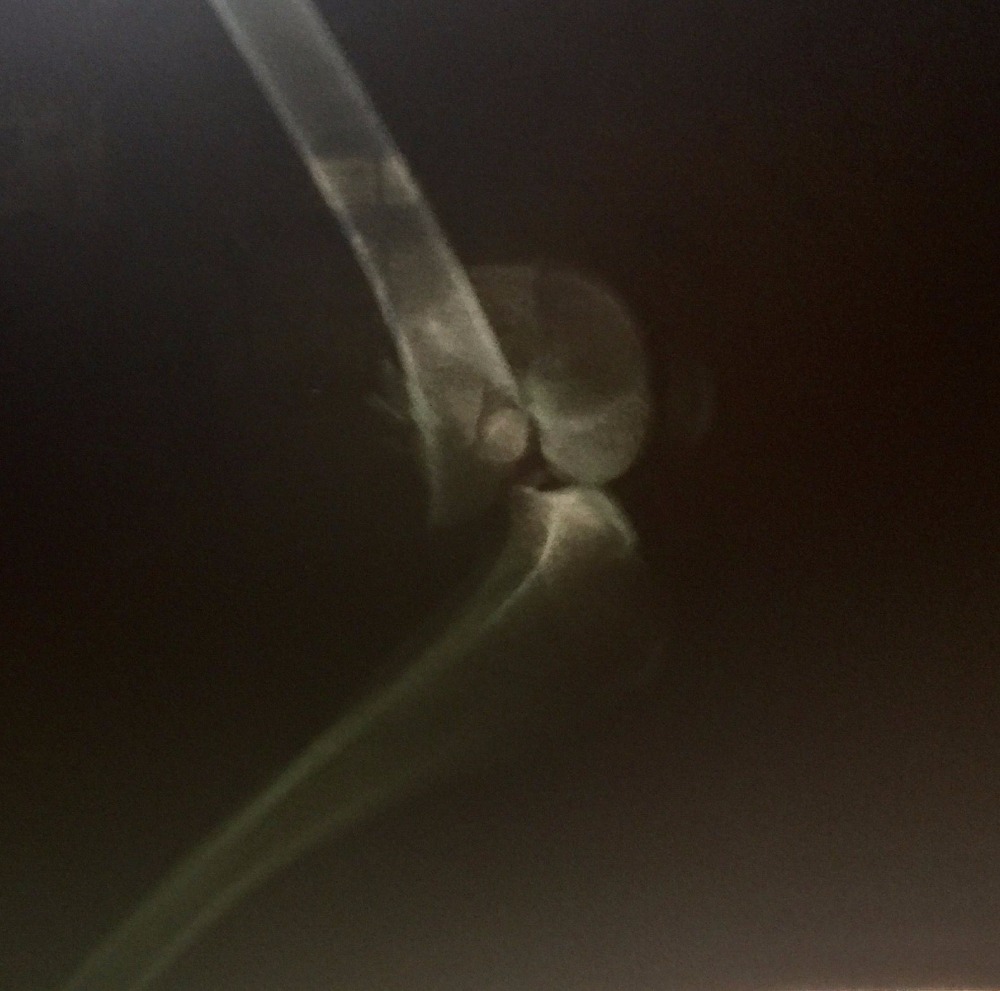

First, I want to thank everyone for their interest in helping this sweet girl. "Morgan" as she has been dubbed, was found on the side of the road (HWY 64 going into Morganton, NC) on 4/23/2016. It was super rainy and cold, and I was headed to Morganton to the feed store. We (my fiance and I) passed a dog sitting only 2-3 ft from the road in the pouring rain. I knew no dog would be sitting on the side of a super busy hwy in the wet and cold for no reason. We turned around and I jumped out of the car as quickly as possible, because we couldn't fully pull out of the road due to a ditch. I approached the dog and immediately realized my worse fears, that she had been hit. Without hesitation I immediately scooped her up, and this is where the story leads us. First off "Morgan" is extremely thin. No microchip, only a lime green collar with no tags. Looks to be (and comfirmed by vet) full-blooded Border Collie. Today she had X-rays and it was confirmed she has a fractured femur just above the knee on the right side, and another break to the bone that connects to the spine on the left side, and a fractured pelvis. She will require surgery and will be referred from the initial attending vet to someone for qualified to perform the surgery, because of the positioning of the femur break. She will require a plate in the femur. We are currently waiting on info from the Orthopedic Specialist of the initial vets choosing, and I will update as I get more info. Intitial vet believes surgery costs o be anywhere from $1200-$1800 (could be more). I WILL NOT give up on this girl, even if her owners have. If you are unable to help financially, prayers and good wishes are just as important and just as appreciated. Initial attending Vet is Dr. Pam Poteat at Forest City Animal Hospital in Forest City, NC. If you would like to confirm they do have a Facebook page with their phone number listed, but I will not list it here out of respect for them. The Orthopedic Surgery will be performed as soon as we can get a refferal and an appt. The Community Pet Center (a 501c3) organization will also be accepting donations on behalf of Morgan for those that would feel more comfortable donating to an organization rather than an individual. I would also like to speak on behalf of Morgan, she has been nothing but an angel and extremely trusting of me from the very beginning of our journey together, and she deserves to live out a long, healthy happy life. She is still very young and has so much left to see and do. Thankyou so much from the bottom of my heart.

Met with the surgeon that was to repair the broken femur this afternoon, and it is concluded that she will need a plate in her pelvic bone and her femur. He will not be able to perform the pelvic surgery and therefore she will have to go a Orthopedic Specialist. Cost has escalated from $1,200-$1,500 to now $2,000-$5,000 (not including aftercare). I will not be able to pay for this surgery in full, but I'm telling you this dog deserves it. At least half of the $5,000 needs to be raised in order to proceed, and we have very little time. If the money is not raised in time (by the end of 4/25/17) I will refund in full the money to all that have donated. Please, Please I beg of you to help me save her life.